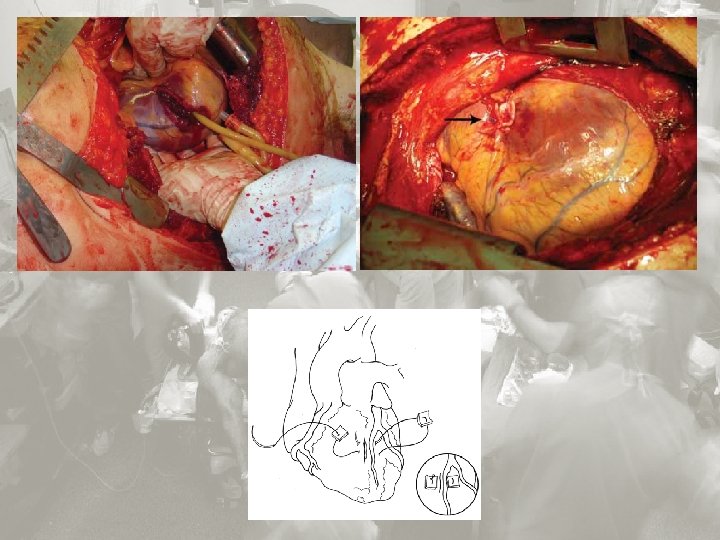

Wskazania do „damage control surgery”: Ciężkie obrażenia jamy brzusznej – kl. piersiowej Złamania miednicy z rozległym krwiakiem zaotrzewnowym Znacznego stopnia uszkodzenia wątroby Obrażenia penetrujące dwunastnicy i trzustki Znaczne uszkodzenia (naczyń, narządów, jelit ) Niska rezerwa fizjologiczna Temperatura < 35ºC p. H < 7, 2 Kwas mlekowy> 5 mmol/L Czas protrombinowy < 50% Ciśnienie skurczowe < 90 przez okres >1 hour Krwawienie z utratą 4000 ml krwi Koagulopatia. Rozsiane krwawienia nie wywołane urazem mechanicznym. Damage control surgery JESÚS MÁRQUEZ ROJAS 1, GERARDO BLANCO FERNÁNDEZ 2, DIEGO LÓPEZ GUERRA 2 1 Servicio de Cirugía General y del Aparato Digestivo, Hospital San Pedro de Alcántara, Cáceres, Spain. 2 Servicio de Cirugía General y del Aparato Digestivo, Hospital Infanta Cristina, Badajoz, Spain.

Damage control in the injured patient Jeremy M Hsu , Tam N Pham Department of Surgery, University of Washington, Harborview Medical Center,